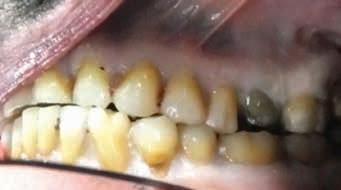

Scene Description: An unidentified Hispanic male was found by a worker mowing grass near the back parking lot of a Domino’s restaurant in Ft. Worth, Texas, on 6-28-2022. The decedent was lying unresponsive in a supine position on the pavement between a dumpster and a cargo shipping container when Ft. Worth police arrived at the scene. Video surveillance obtained from the restaurant caught the decedent moving around on camera near the dumpster at 1800 hours on 6-28-2022. The decedent was clad in pants and a belt. No signs of medical intervention were observed, and brown emesis was present around the decedent’s mouth. No foul play was suspected.

Dental Evidence Recovered: Maxilla and Mandible

Right Left

Right Lateral View

Left Lateral View

Periapical Tooth #3 (Root Canal Treatment)

Periapical Tooth #14 (Root Canal Treatment)

#3 #14